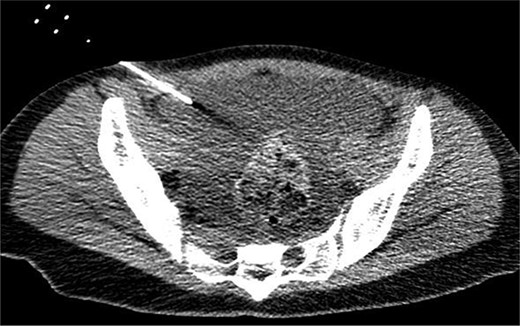

Endoscopic retrograde pancreatography (ERP) was performed, and contrast leakage was observed in the pancreatic body, leading to the diagnosis of grade III pancreatic injury (Fig. 3a). Although the guidewire was successfully passed beyond the injury site to the caudal pancreatic duct, cannula passage proved challenging (Fig. 3b). Consequently, a 5 Fr EPS was placed in the region of the pancreatic head (Fig. 3c).

ERP and EPS on the fourth day. (a) Leakage of the contrast medium was observed in the pancreatic body, leading to the diagnosis of grade III pancreatic injury. (b) The cannula had difficulty passing through the injury site; however, the guidewire was observed to have passed beyond the pancreatic duct injury site at the pancreatic tail. (c) A 5 Fr-5 cm EPS was placed in the region of the pancreatic head.